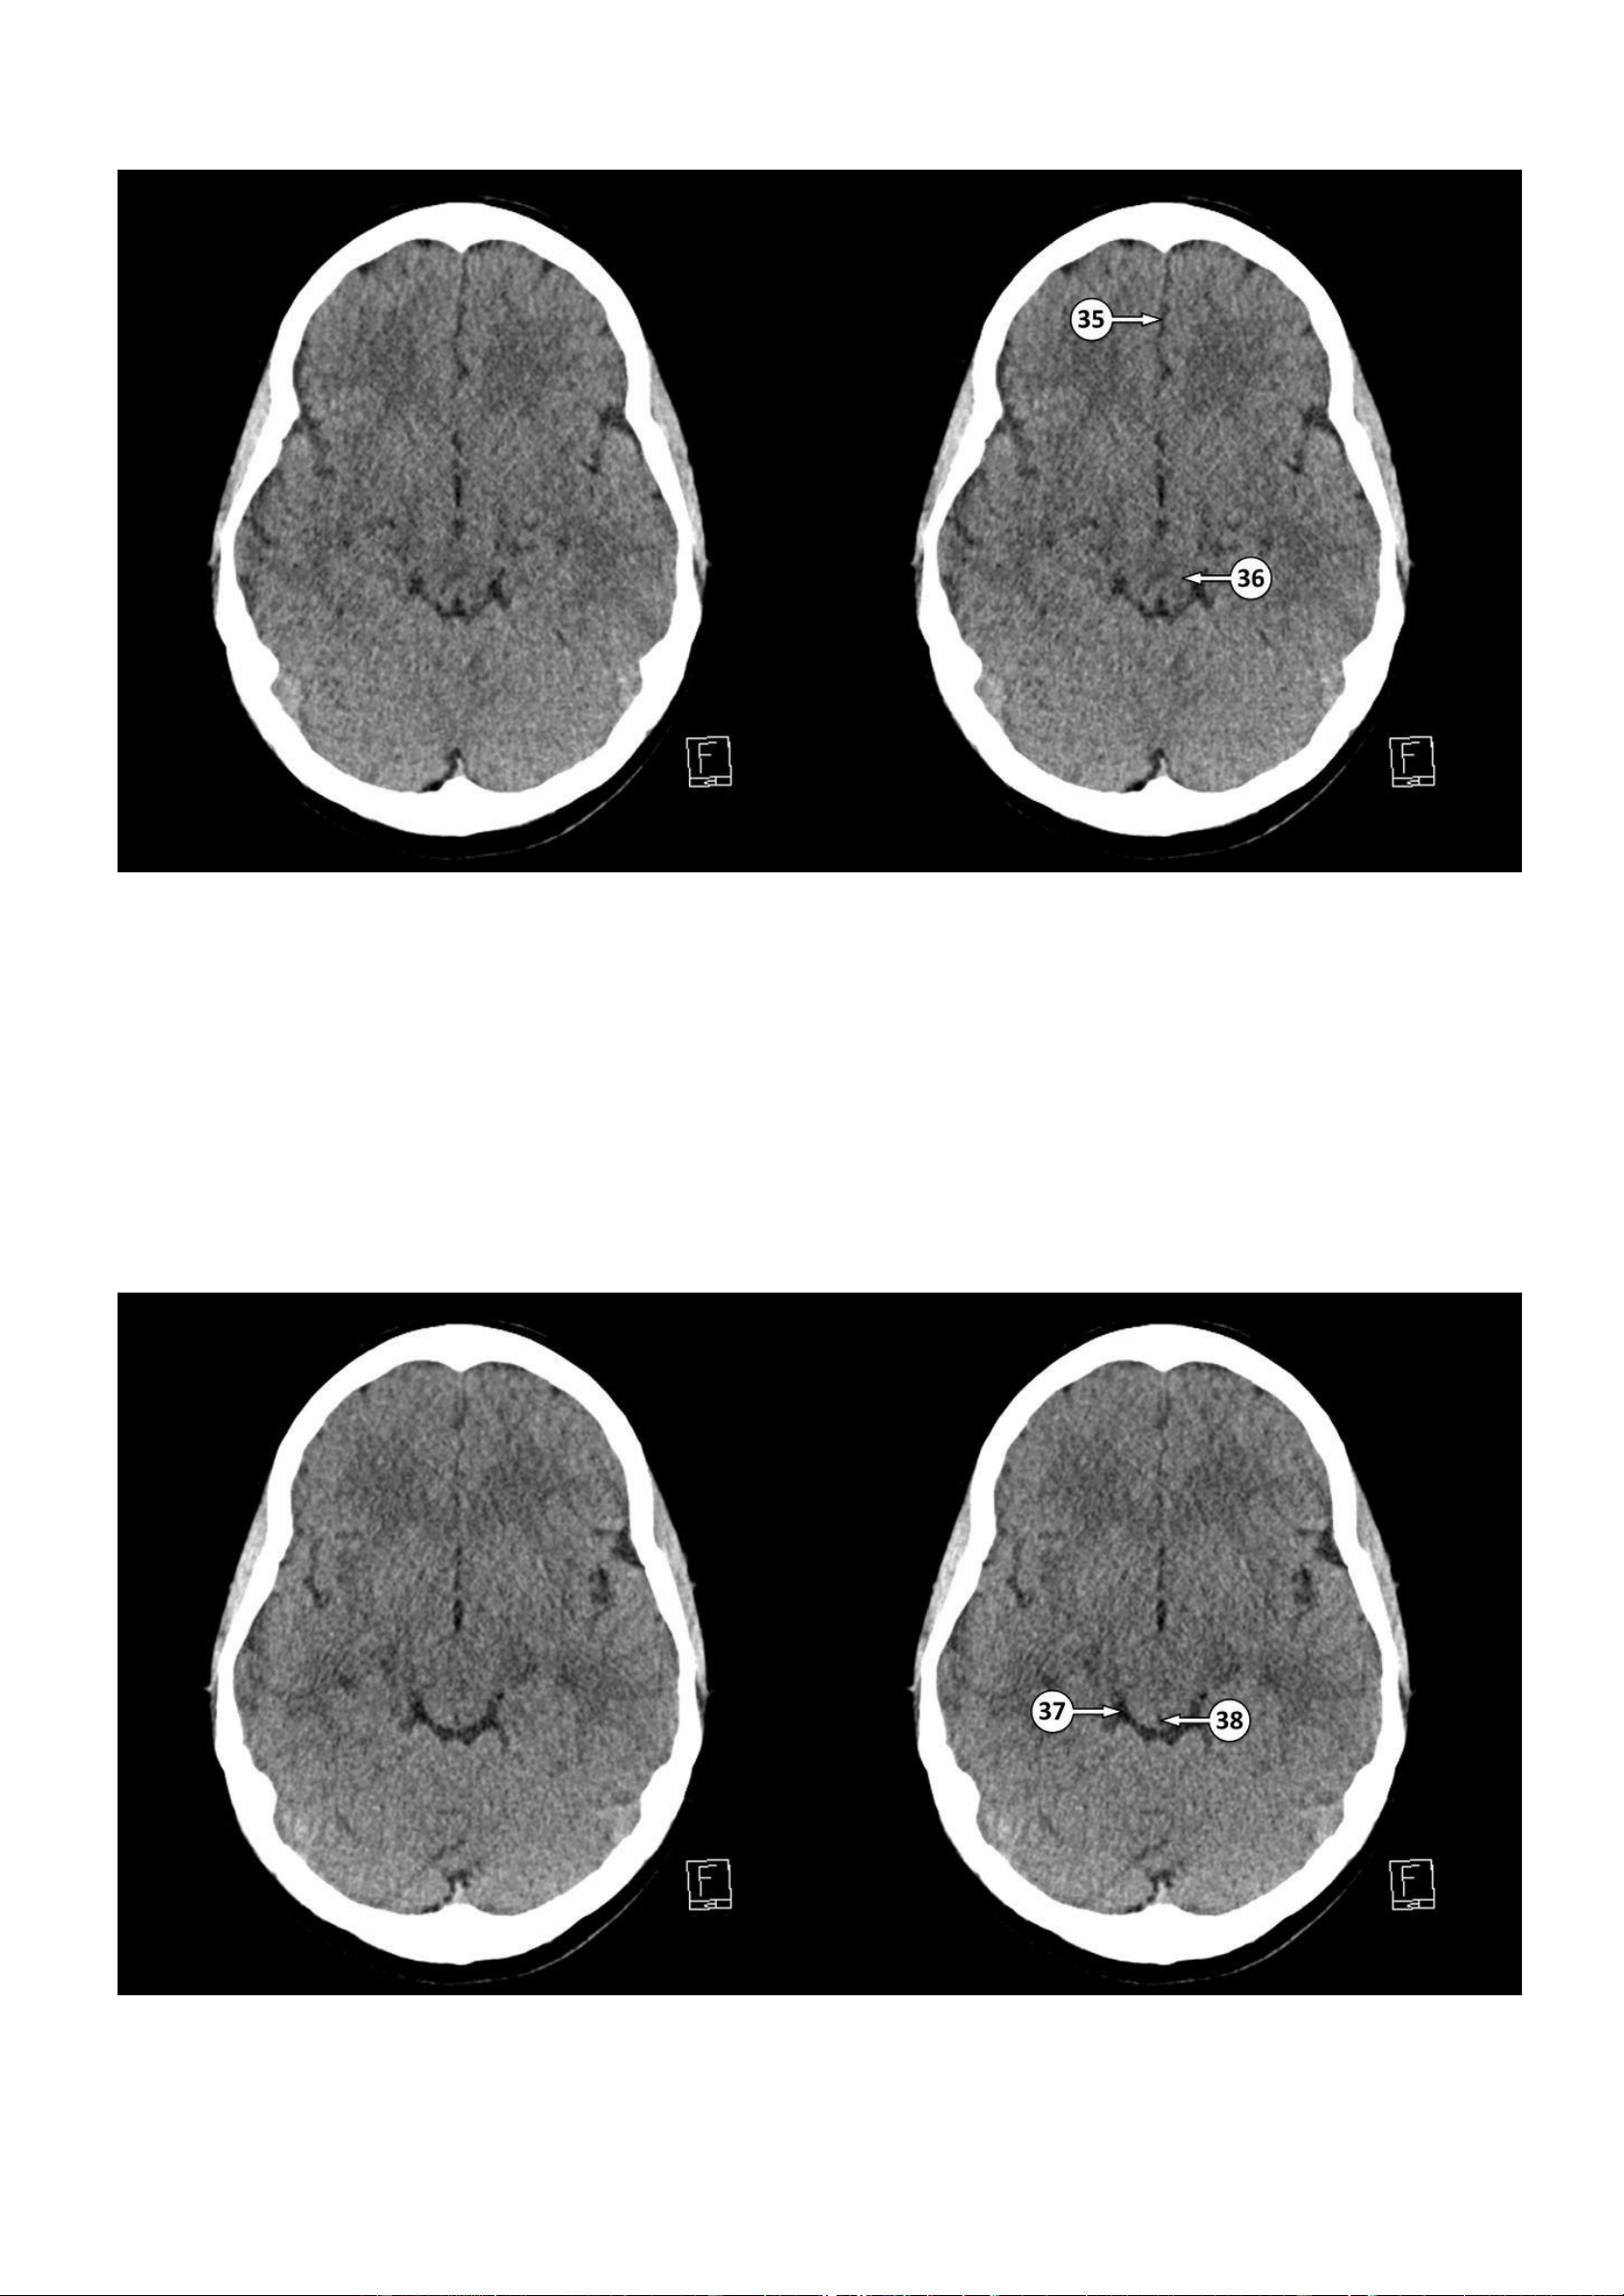

Thảo Thảo & Bé Nghìn Dặm ▪ Số 39: Não thất III

▪ Số 40: Củ não sinh tư dưới

▪ Số 41: Hợp lưu các xoang tĩnh mạch màng cứng

▪ Số 42: Cánh tay trước của bao trong

43: Lỗ gian não thất (lỗ Monro) 44: Vỏ não thuỳ đảo lOMoAR cPSD| 22014077